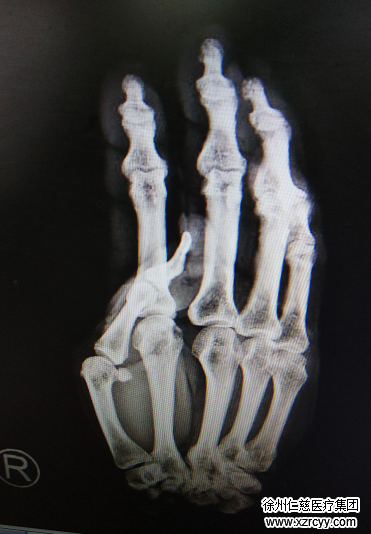

病人来到医院已经由于失血太多,全身湿冷,神情淡漠,经手外科三病区主治医生李刚诊断,赵阿姨右手腕离断,前臂血管、神经、肌腱损伤严重,右上臂肱骨骨折……

“啪——”手术室无影灯亮起,李刚医师手术小组争分夺秒,为患者实施“右手腕清创再植+右手、右前臂切开减压术”。手术中,医生先固定骨折断端,吻合动静脉让肢体通血,然后一一修复断裂的肌腱、肌肉及神经……知道最后一针缝合完毕,已经是第二天凌晨4点钟,经过近8个小时的努力,术中输血1600ml,手术成功!